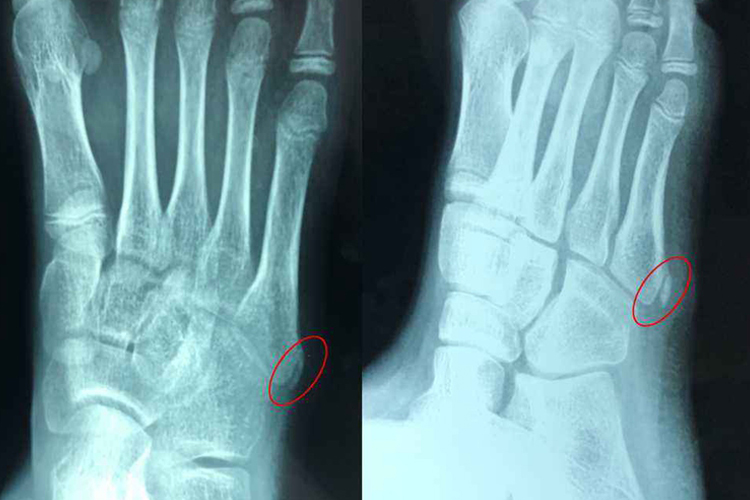

儿童的骨骼正处于生长发育期,第五跖骨位于跗骨与趾骨间,处于近侧基底位置,前足外翻、内收肌腱牵拉、直接暴力使第五跖骨近端容易形成骨骺或骨折情况,运动时应注意避免剧烈活动。

[1]滕君.青少年第五跖骨近端骨骺与骨折在数字X线摄影特点及临床意义[J].中外医疗,2018,37(32):3.

[1]刘建立,刘吉华,来洪建,等.青少年第五跖骨近端骨骺与骨折的数字X线摄影特点探讨及临床意义[J].实用医学影像杂志,2015,16(5):3.